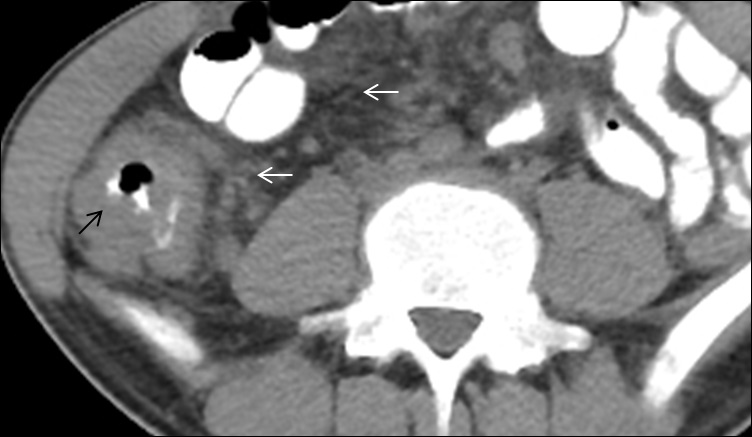

Tubercular peritonitis

Peritoneal involvement is frequently seen in all forms of abdominal tuberculosis. There are three main types of tubercular peritonitis is given [5]. (A) The wet type is in which a large amount of free or loculated viscous fluid is seen. CT findings in this type of peritonitis include high attenuation free fluid (HU value between +25 to +45; signifies high protein and cellular content), (B) the fibrotic fixed type of peritonitis, which is less common and is marked by omental masses, matted mesentery or bowel loops and sometimes loculated ascites, (C) the dry or plastic-type, which is unusual and on CT scan it appears as caseous nodules, fibrous peritoneal reaction, and adhesions. All these described CT features may be confused with peritoneal carcinomatosis [6]. Therefore few features like minimal thickening and enhancement signify TB peritonitis, (Figure 2A,2B) while nodular or irregular thickening implies carcinomatosis. TB peritonitis has a few other findings like macronodular mesenteric deposits (>5 mm), fibrous wall covering the omentum (cocoon abdomen) (Figure 2), and peritoneal or extraperitoneal masses with internal calcifications. Few studies also state that the spreading of inflammation through the peritoneal to the extraperitoneal compartment is specific for TB infection [7].

Figure 2: Two patients, a 35 years old male and a 40 years old female presented with vague pain abdomen, on & off fever and abdominal distension. Contrast-enhanced computed tomography (CECT) abdomen scan demonstrates various forms of involvement in abdominal tuberculosis. (A & B) Axial images from the postcontrast venous phase illustrate peritoneal thickening (white arrow), high density exudative peritoneal fluid (HU=35 to 45) (black arrow), and diffuse mesenteric fat stranding (thick white arrow). Peritoneal fluid cytology demonstrated the presence of lymphocytes, and biochemistry revealed high adenosine deaminase enzyme value (83IU/L), labelling the diagnosis of TB in the endemic regions. The patients underwent a therapeutic ascitic tap and started on antitubercular drugs